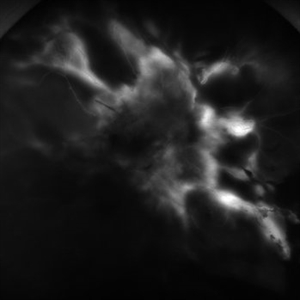

Severe Proliferative Diabetic Retinopathy

Jan 10 2024 by Ahmad B. Tarabishy, MD

33 year old female with 1 month history of vision loss right eye. Severe PDR was noted with VH and a TRD with severe FVP present OD.

Photographer: Sharon Story, Lakeland Eye Clinic

Imaging device: Optos

Condition/keywords: diabetic blindness, fibrovascular proliferation, nonperfusion diabetic retinopathy, peripheral retinal nonperfusion, proliferative diabetic retinopathy (PDR), tractional retinal detachment